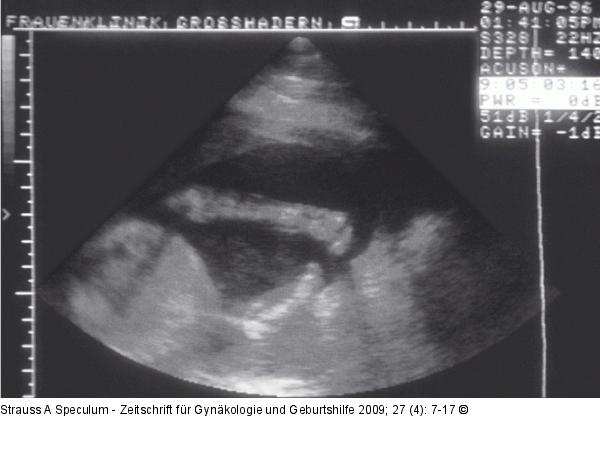

Abbildung 3: Fetus - Extremitätendefekt Extremitätendefekt beim Fetus: Bei großem Uterus myomatosus in graviditate sonographische Darstellung (22. SSW) des rechten kindlichen Armes. Distal der Handwurzel vollständiges Fehlen der rechten Hand. |

Extremitätendefekt beim Fetus: Bei großem Uterus myomatosus in graviditate sonographische Darstellung (22. SSW) des rechten kindlichen Armes. Distal der Handwurzel vollständiges Fehlen der rechten Hand. |